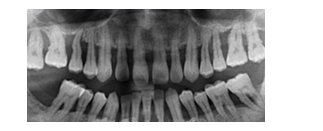

患者女性,59歲,右側(cè)后牙咀嚼無力,刷牙時牙齦出血。無系統(tǒng)性疾病。口腔檢查顯示全口多數(shù)牙牙石(++),牙齦紅腫,探診出血,牙周袋袋深4~6mm,右下后牙有Ⅰ~Ⅱ度松動,X線片如圖所示:

【答案解析】根據(jù)患者臨床表現(xiàn)和X線片檢查,可明確診斷為慢性牙周炎。